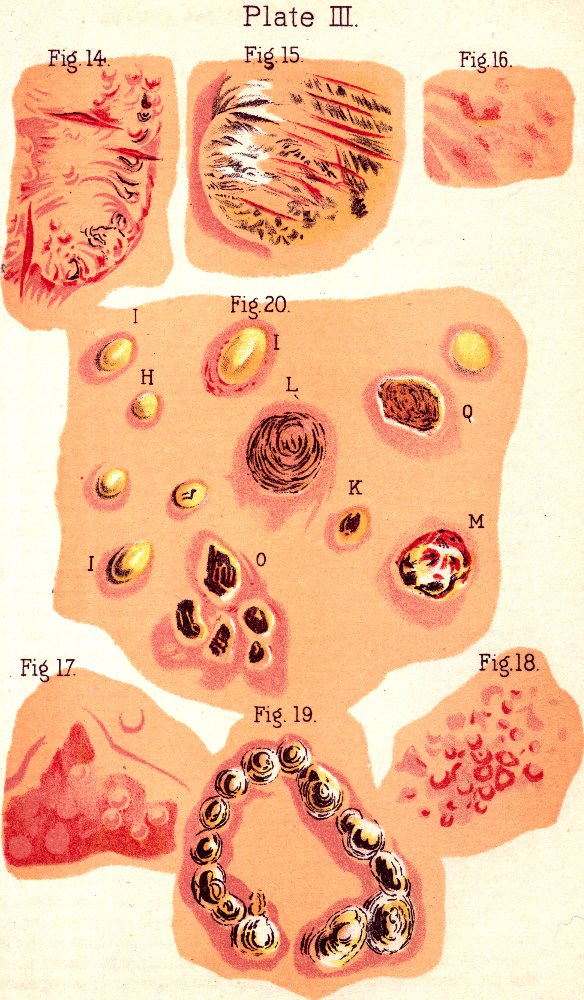

Fig. 14. Backbone, spinal

column, or vertebral column. All animals possessing such a row of bones are

called vertebrates. Above b are the cervical (neck)

vertebræ; b to c, dorsal (back) or chest

vertebræ; c to d, lumbar (loins) vertebræ;

d to e, sacrum; e to f, coccyx.

Fig. 15. A representation of the pelvic bones. e. The

lumbo-sacral joint. 2. The sacrum. 3. Coccyx. 1, 1. The

innominata. 4,4. Acetabula.

Fig. 16. 1. Portions of

the backbone. 2. Cranial bones. 4. Breast-bone. 5. Ribs.

7. Collar-bone. 8. Arm-bone (humerus). 9.

Shoulder-joint. 10, 11. Bones of the fore-arm (ulna and radius).

12. Elbow-joint. 13. Wrist-joint. 14. Bones of the

hand. 15, 16. Pelvic bones. 17. Hip-joint. 18. Femur.

19, 20. Bones of the knee-joint. 21, 22. Fibula and tibia.

23. Ankle bone. 24. Bones of the foot.